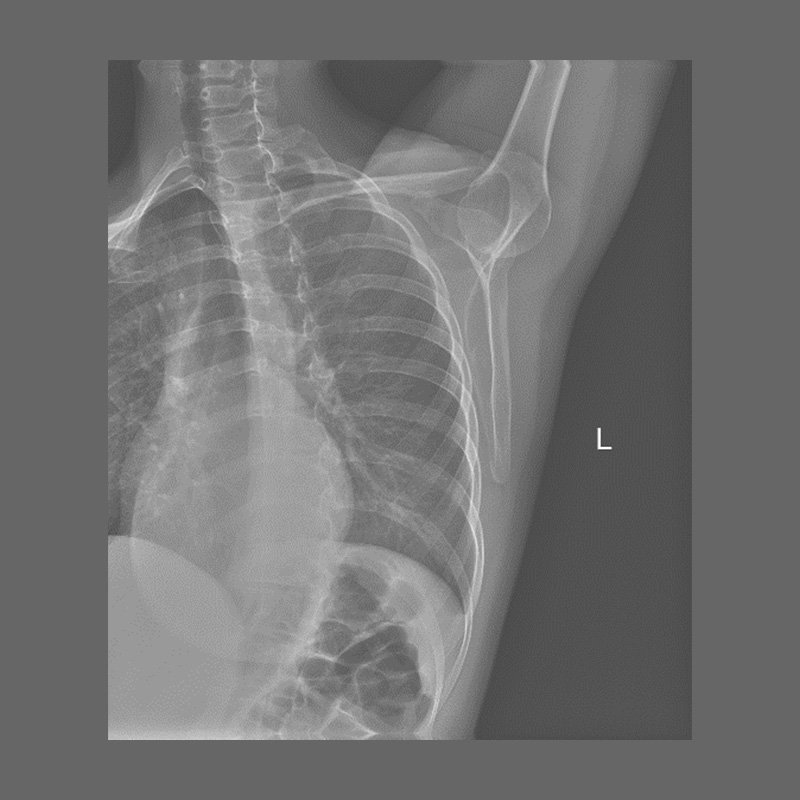

КЛІНІЧНА ГАЛЕРЕЯ GENÈVE 40M: